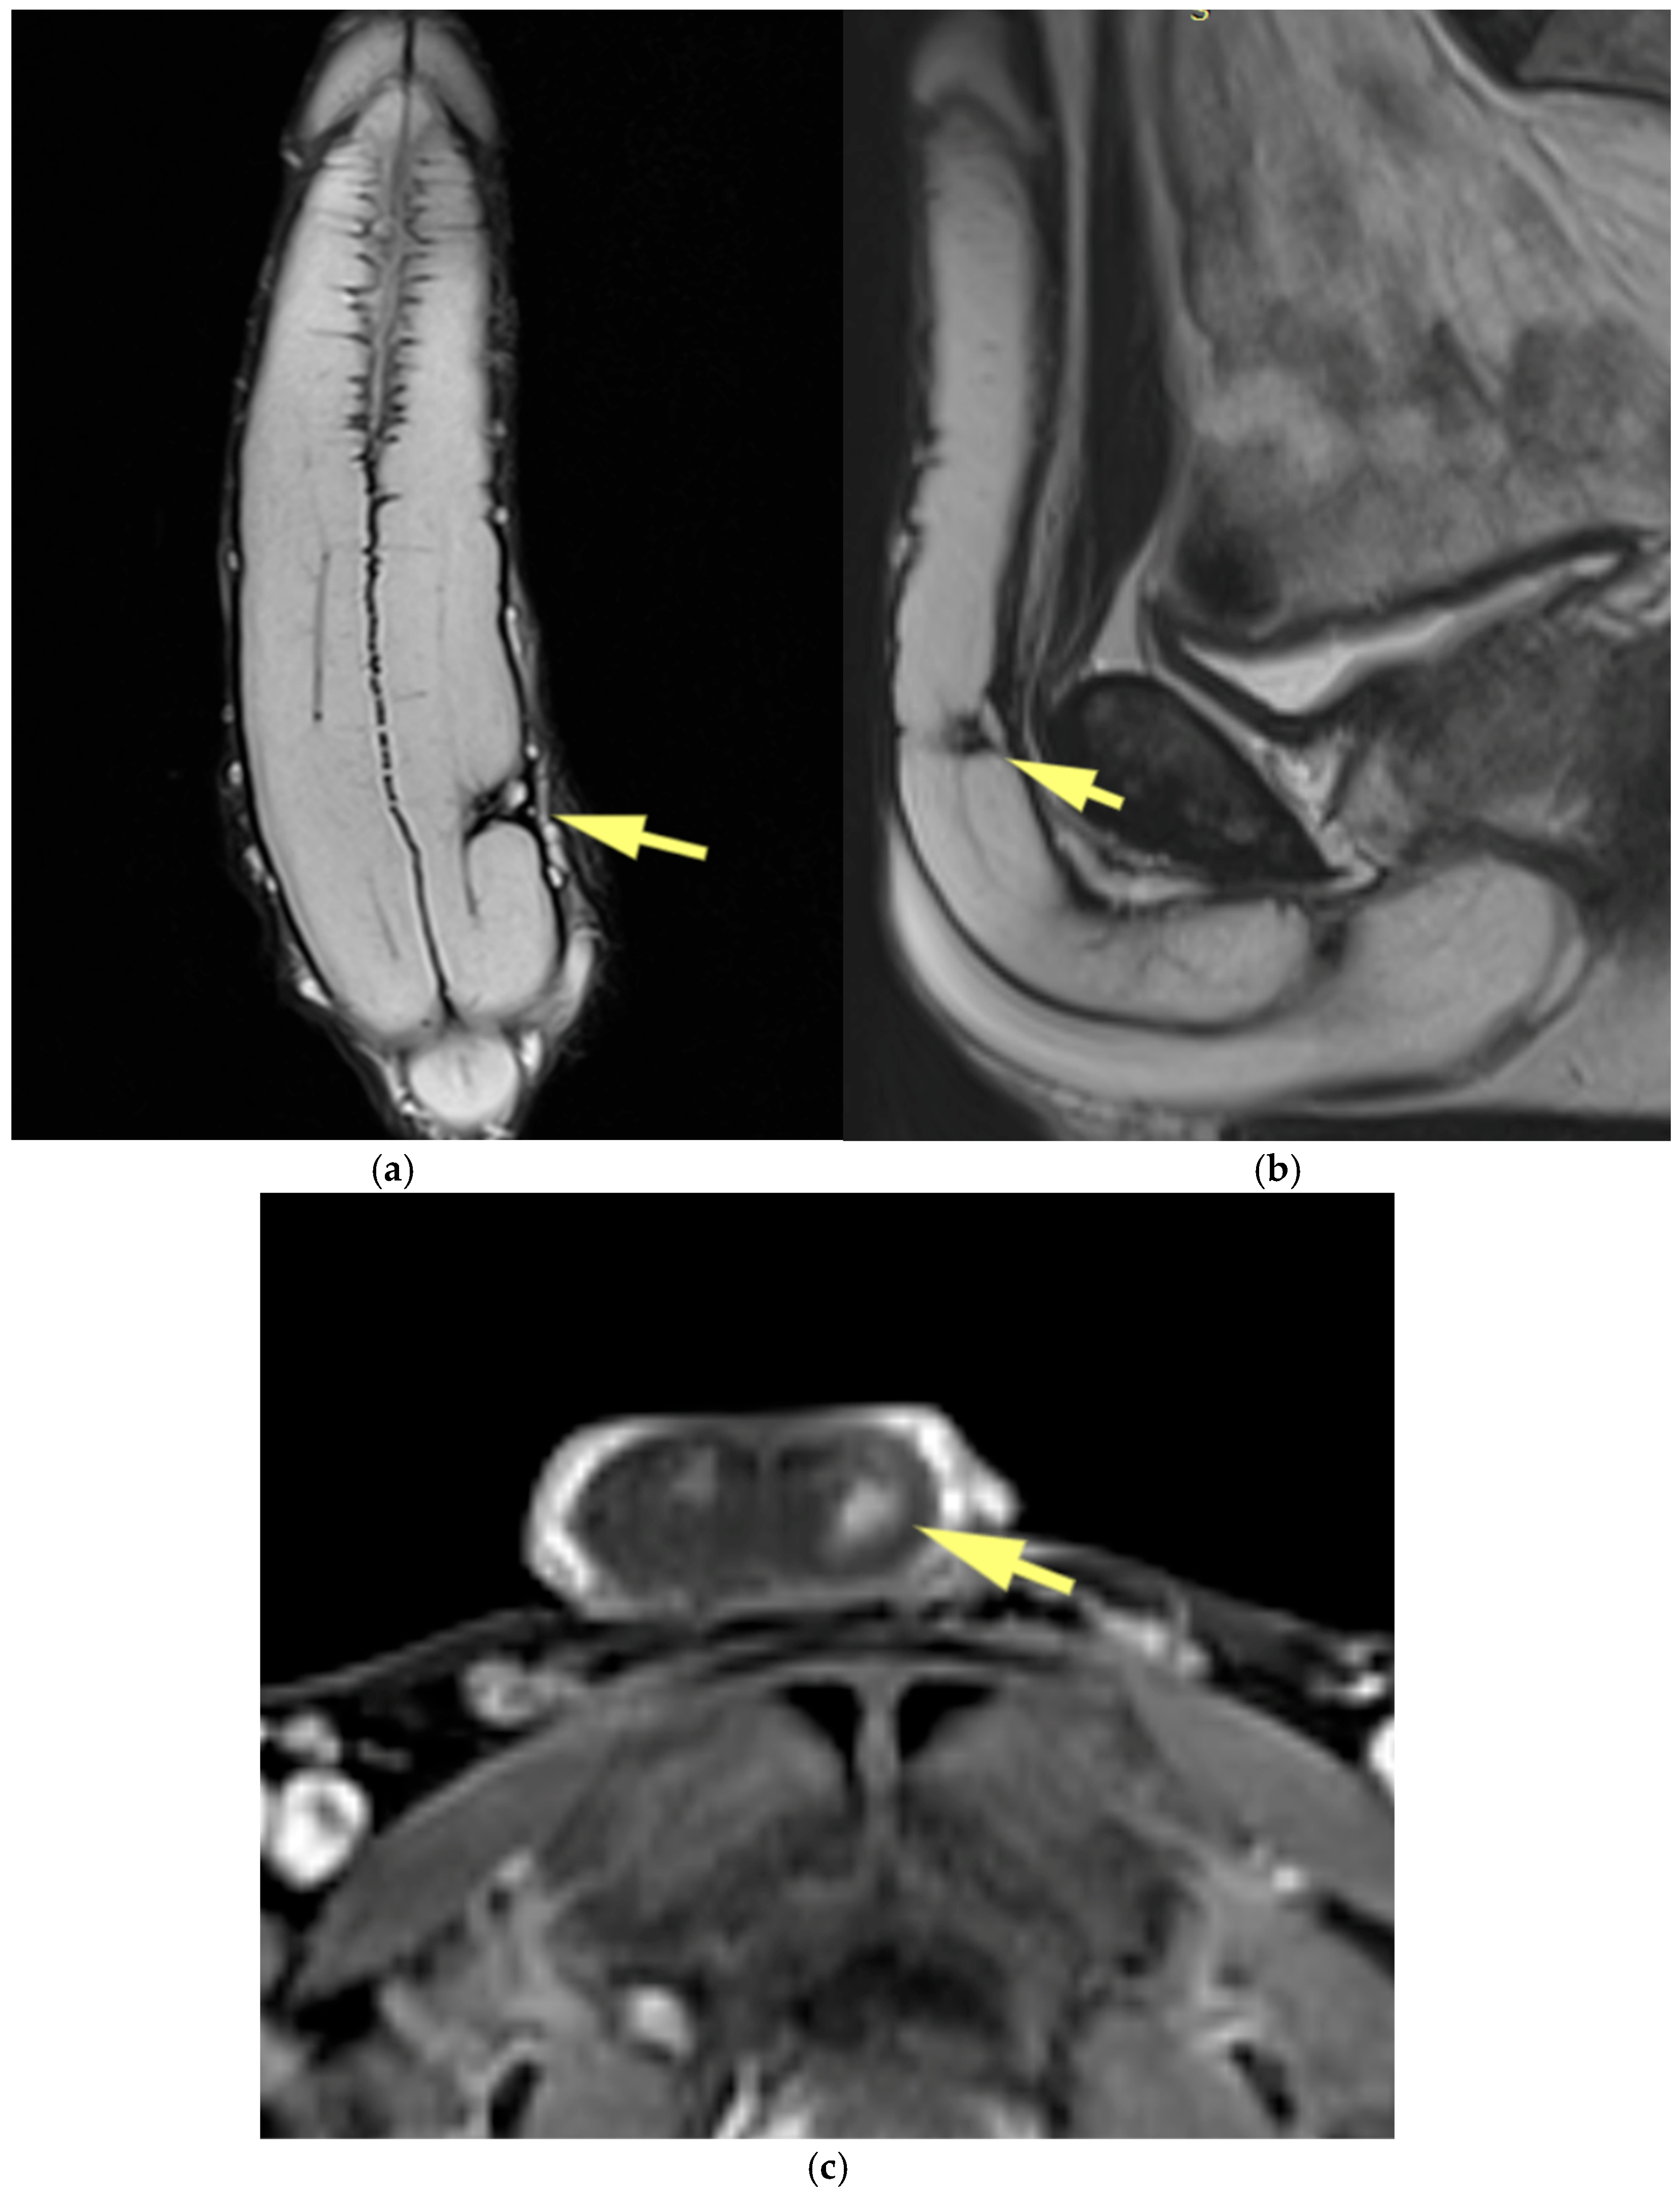

4.1. Penile Neoplasms

4.2. Penile Trauma

4.3. Priapism